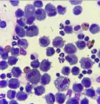

Idiopathic lymphoplasmacytic rhinitis